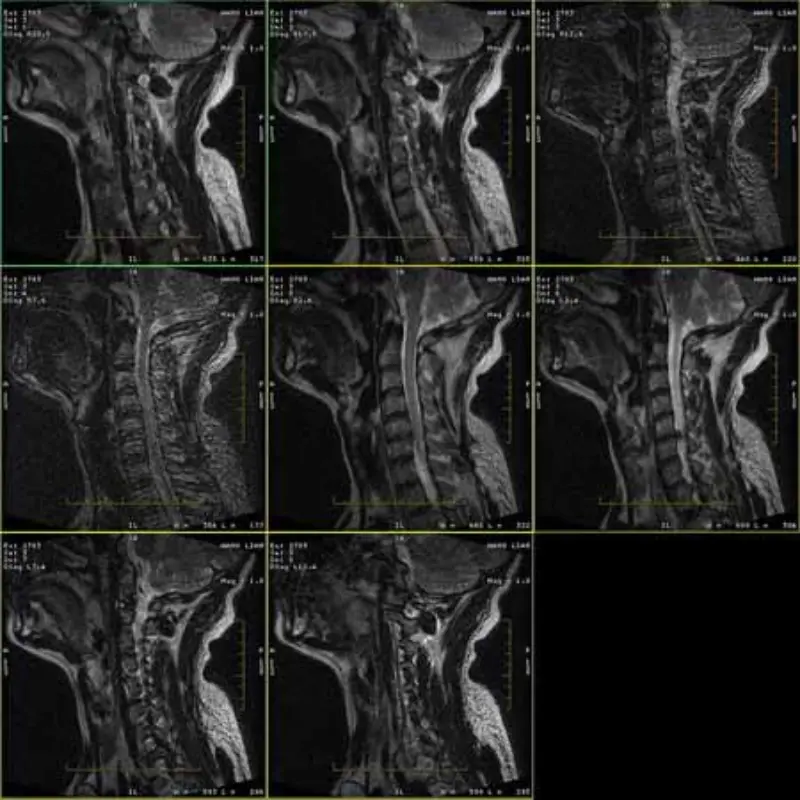

Gambar saka FRFSE lan GRE protokol wis memedi lan kadhangkala gambar SNR kurang katon ing siji seri. Nanging gambar protokol SE iku normal.

Mangga deleng lampiran gambar.